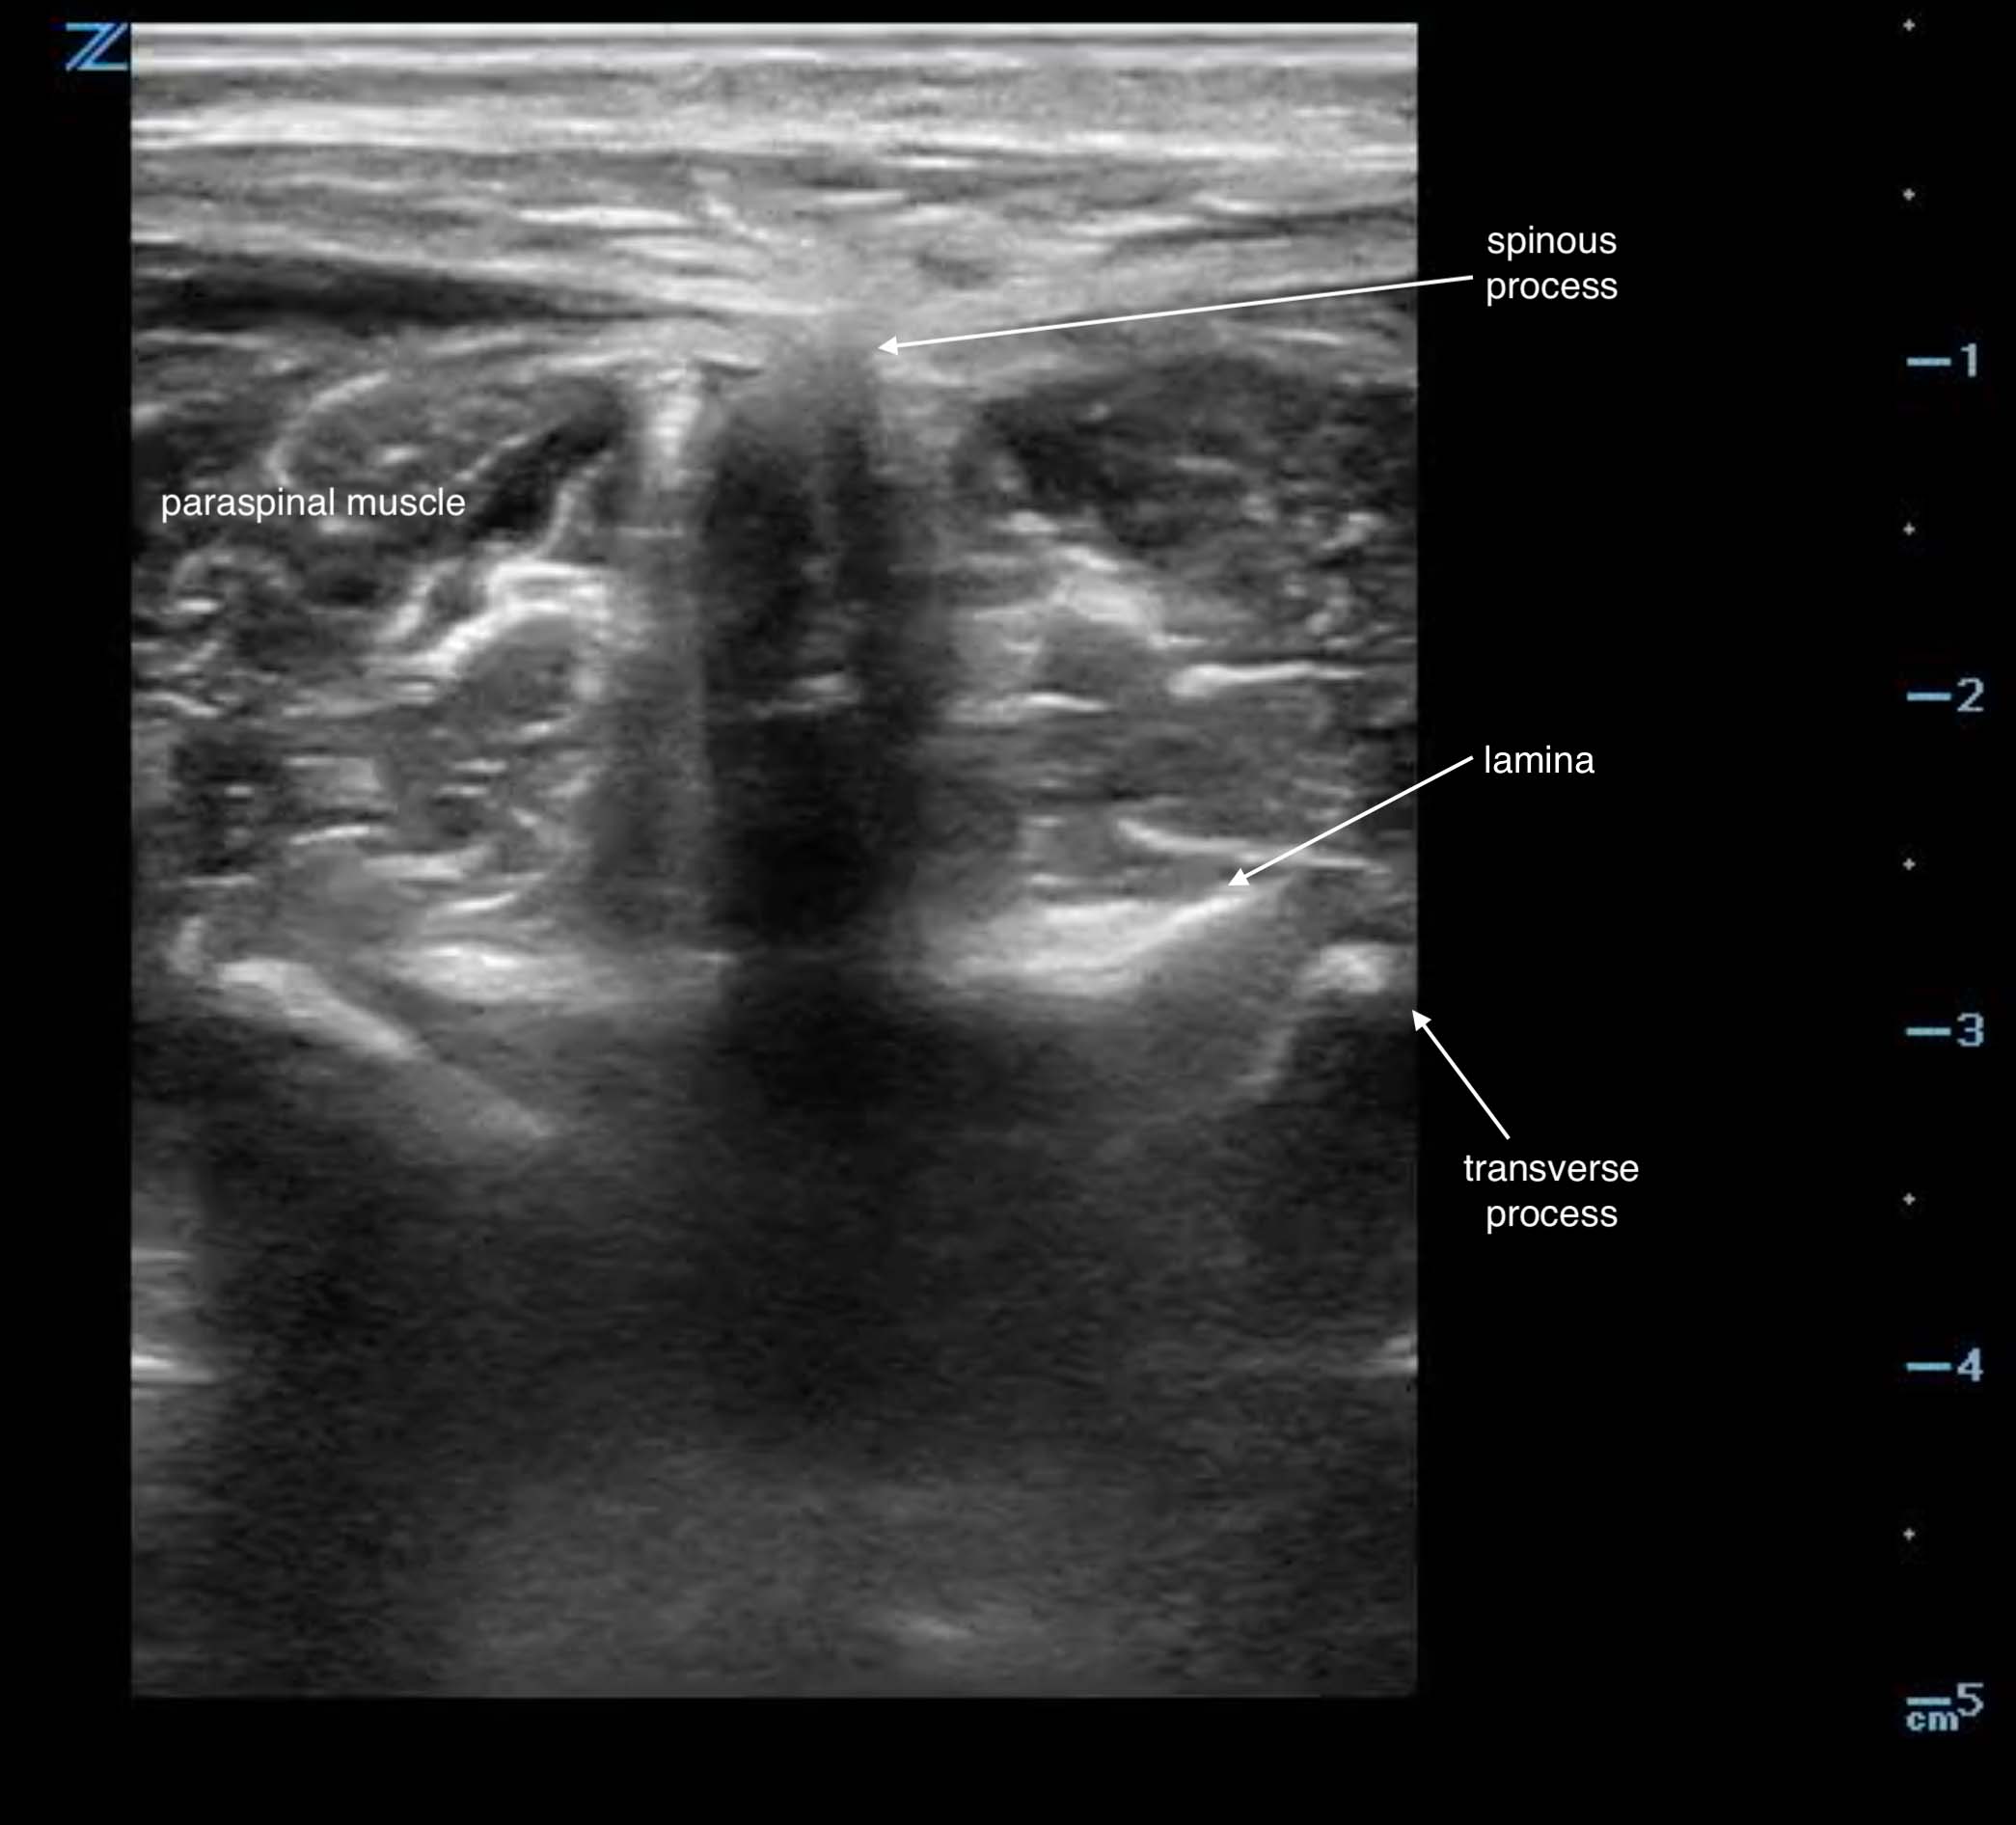

- After visualizing the line formed across the superior iliac spines, scan in the transverse plane to the spinal column to identify the crescent shaped hyperechoic spinous process with underlying shadow. You may identify the paraspinal musculature on either side of this bony structure in the transverse view. (Fig. 2)

- Figure 2. Transverse view spinous process in adult